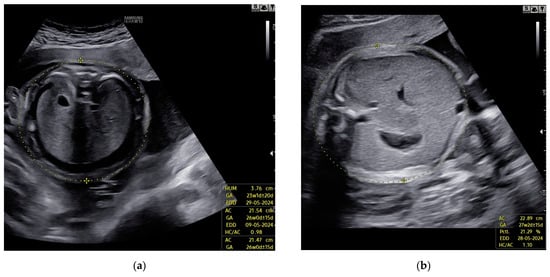

Despite a slight improvement in Doppler findings, no resolution of fetal hydrops was observed (Figure 2).

Figure 2. Case 4: Edema of fetal subcutaneous tissue; no signs of resolution of hydrops; (a) before first intrauterine transfusion, 20 weeks of gestational age; (b) after third intrauterine transfusion, 24 weeks of gestational age.